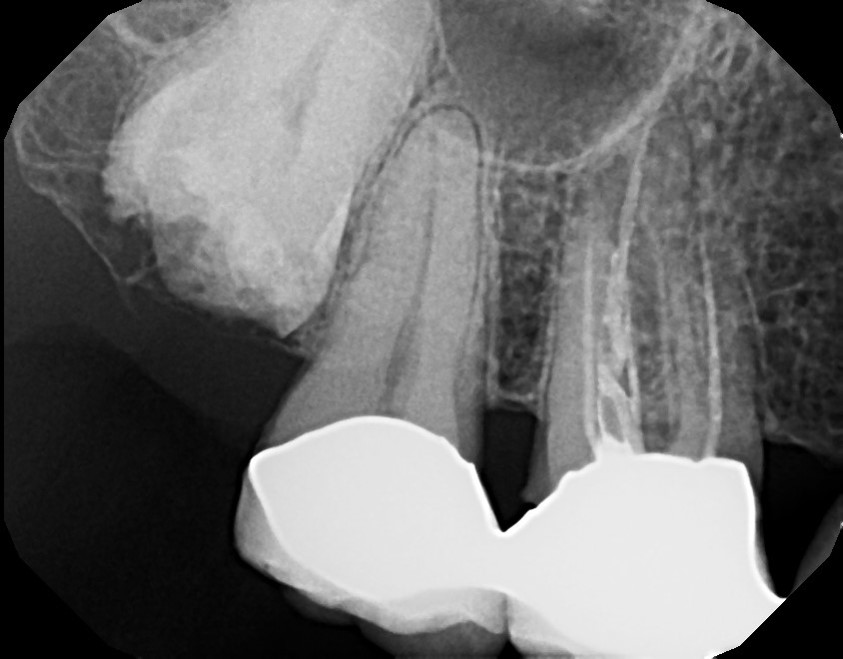

Accurate diagnosis is sometimes the most difficult aspect of daily clinical practice. CBCT has improved the trained practitioner's ability to find hidden periapical pathology, particularly in areas where structures such as the maxillary sinus and zygomatic arch, as well as thick cortical bone, can conceal periradicular lesions (Figure 7 and Figure 8).5-7

Fig 7. 2D radiograph of tooth No. 3.

Figure 7

Fig 8. 3D CBCT image of tooth No. 3 revealing hidden periapical pathology.

Figure 8